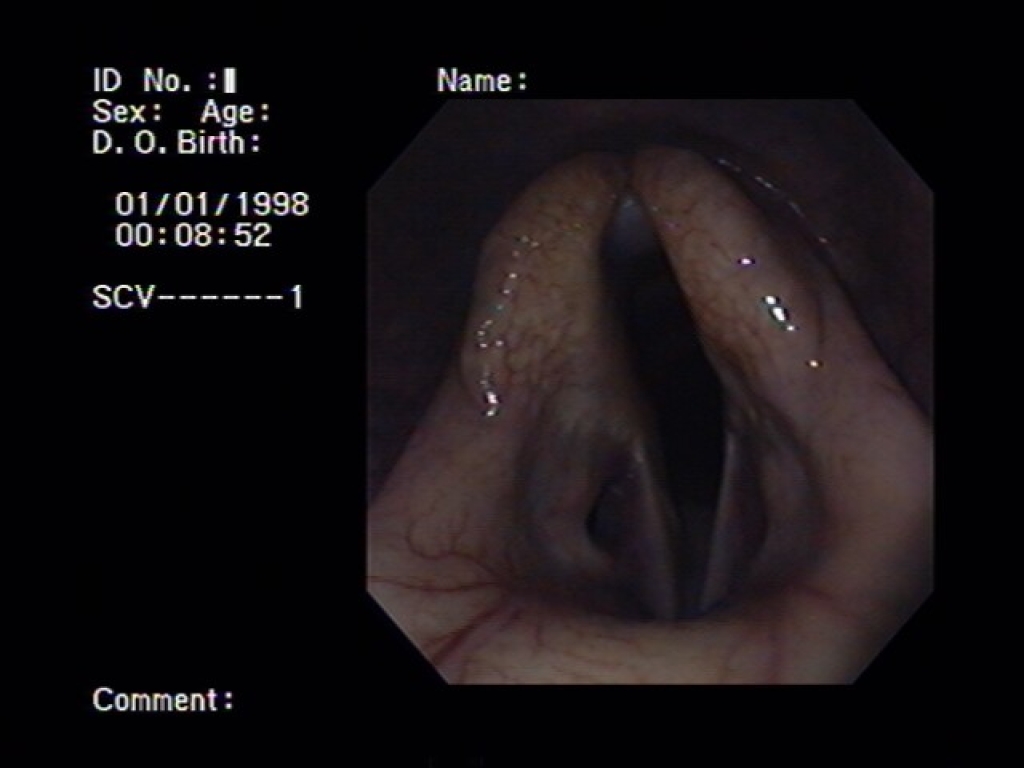

Bij een bronchoscopie wordt er via de neus een dunne slang met een camera naar binnen gebracht. Via deze camera kunnen we de luchtwegen bekijken.  We beginnen meestal in de keel. We kijken dan naar de uitmondingen van de luchtzakken, het strottenhoofd, de stembanden en het slijmvlies van de keel. Indien nodig kunnen we ook in luchtzakken kijken met de bronchoscoop. Vervolgens kunnen we met de bronchoscoop tussen de stembanden door de luchtpijp in. In de luchtpijp kijken we hoeveel slijm daar aanwezig is en of er nog andere tekenen zijn van een ontsteking. Meestal kijken we al laatste naar de neusgangen en neusholte. Op het moment dat we slijm of andere afwijkingen vinden kunnen we hier via de bronchoscoop ook gelijk een uitstrijkje van maken voor bacterieel onderzoek.

Linksbovenin is de keelholte in beeld gebracht. Rechtsboven is het strotteklepje met de stembanden daarachter van dichtbij in beeld gebracht. Het linker plaatje is van de luchtpijp.